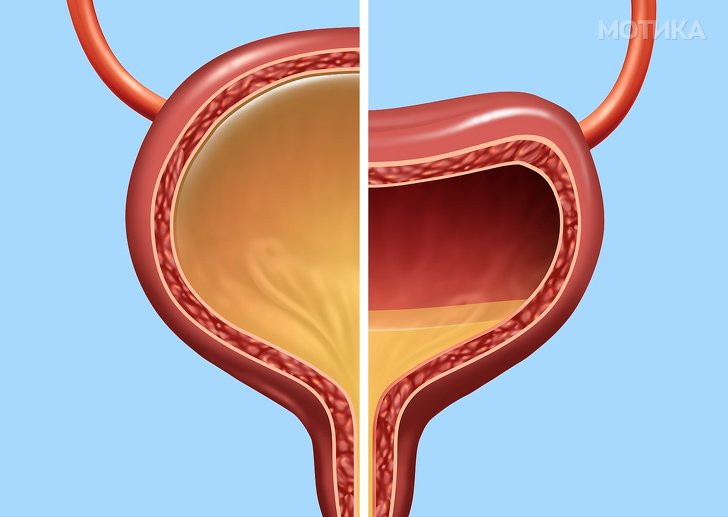

6. Мочниот меур

- Овој орган изгледа како шуплива торба и може многу да се растегне. Може да собере и урина до скоро еден литар.

- Возрасниот мочен меур изгледа како круша во однос на големината и формата.